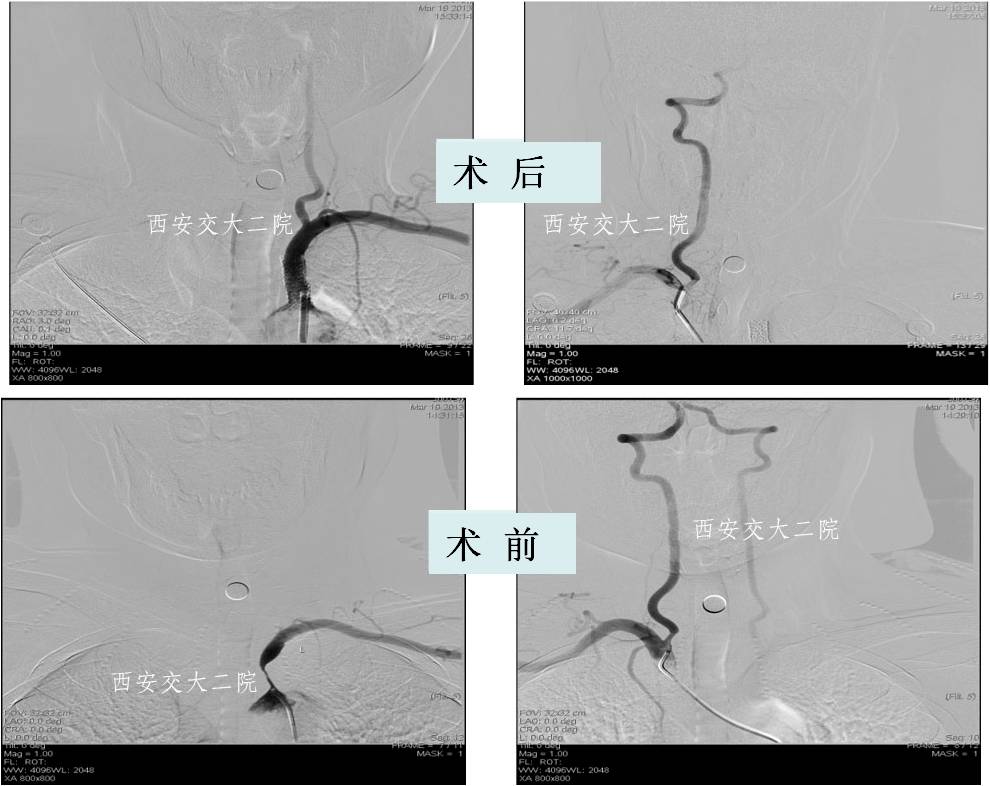

Case 1 颈内动脉C1段急性闭塞(2009年)

》男,70岁,突发右侧肢体无力3小时,DSA提示左侧颈内动脉起始段闭塞。

Case 2 左侧大脑中动脉溶栓+支架 (2009年)

》男,44岁,突发言语不能,右侧肢体活动不灵2小时。

》尿激酶10万后MCA未通,给予Apollo支架植入。

Case 1 颈内动脉狭窄支架成形术(2009年)

》男,52岁,发作性左侧肢体无力2周,右ICA开口狭窄支架后。

Case 2 颈内动脉眼动脉段狭窄(2010年)

》女,51岁,左侧肢体无力1月,加重20天,DSA示右侧颈内动脉眼动脉段狭窄80%。

Case 3 大脑中动脉支架成形术(2012年)

》男,61岁,右侧肢体不自主运动12天。

Case 4 右侧颈内动脉开口狭窄(2013)

》男,80岁,发作性左侧肢体无力、右眼视物不清1年,药物治疗后仍有发作。